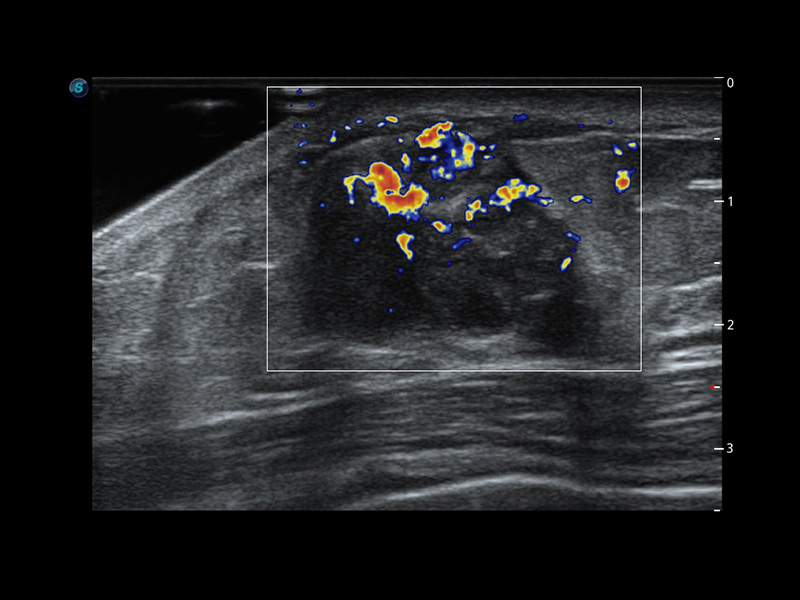

Micro F

Ermöglicht die Visualisierung von mikrovaskulären Strukturen

Micro F bietet eine innovative Methode, um den sichtbaren Fluss in der Ultraschallbildgebung zu erweitern, insbesondere um den langsamen Fluss kleiner Gefäße sichtbar zu machen. Durch die Verwendung eines fortschrittlichen adaptiven Filters und die Akkumulation von zeitlichen und räumlichen Signalen kann Micro F den geringen Blutfluss effektiv von der Bewegung umgebendem Gewebe unterscheiden und die Hämodynamik mit höherer Empfindlichkeit und räumlicher Auflösung darstellen.

• Zervikales schlecht differenziertes Karzinom mit Micro F

• Fetale Pericallosal-Arterie mit Micro F

• Fetale einseitige Kleinhirnhypoplasie mit Micro F

• Fetaler Leberblutfluss mit Micro F